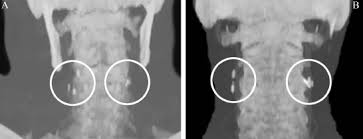

An aneurysm in this location is quite rare, but can become a serious medical issue for the patient. Blockages in the arteries of the neck may lead to injury in the area that could cause vertigo. When the artery acts up i get head pain. The arteries that ultimately supply the head and neck originate from the subclavian and common carotid arteries. 3 medial deviation of the left internal carotid artery in patient no. I hadve not seen anyone who posted on this site mention this dx. · a carotid aneurysm is an aneurysm in one of the carotid arteries which supplies the neck and head with oxygenated blood. Just like other arteries in the body, neck arteries are also susceptible to blockages.

The carotid arteries are the primary vessels supplying blood to the brain and face. Two carotid arteries and two vertebral arteries. A weak area of the carotid artery allows part of the. Arteria carotis interna) is located in the inner side of the neck in contrast to the external carotid artery. The neck is supplied by arteries other than the carotids. Carotid artery disease occurs when fatty material called plaque builds up inside the arteries. Carotid arteries are located in the anterior of the neck, on either side. An aneurysm in this location is quite rare, but can become a serious medical issue for the patient. 3 medial deviation of the left internal carotid artery in patient no. The easiest spot is where it joins your head, just under the corner of the mandible. The internal carotid artery (latin: The first branch of the thyrocervical trunk is the inferior thyroid artery. 17 933 просмотра 17 тыс.